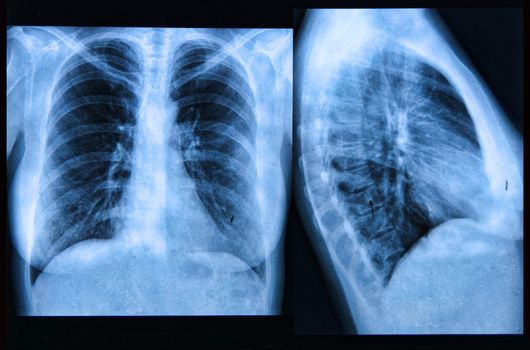

Louth Woman Becomes First Person In Ireland To Receive A Double Lung Transplant

Twenty-year-old Leigh Bagnall is the first person in Ireland to undergo a groundbreaking double Ex-Vivo lung perfusion operation.

Leigh Bagnall, who suffers from cystic fibrosis had the pioneering, new type of transplant carried out at Dublin’s Mater Hospital last year and says it has changed her life.